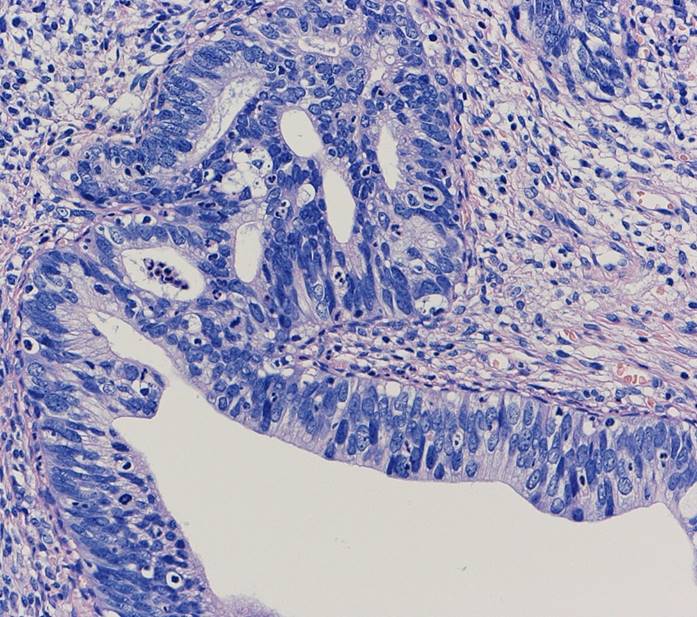

子宮頸部のSCJにおいてクロマチン増量を示す異型上皮が明瞭な

腺管構造や充実性胞巣構造を形成し増生していた。充実性増生を示す成分はN/C比や核分裂像が目立ち、免疫染色ではsynaptophysin、chromogranin A、CD56が陽性であり神経内分泌分化が示唆された。以上の所見より、神経内分泌癌成分を伴う腺癌と診断された。面積的には腺癌成分が8割で神経内分泌癌成分は2割であった。腺癌成分で微小浸潤がみられたが神経内分泌癌成分はin situであった。

腺管構造や充実性胞巣構造を形成し増生していた。充実性増生を示す成分はN/C比や核分裂像が目立ち、免疫染色ではsynaptophysin、chromogranin A、CD56が陽性であり神経内分泌分化が示唆された。以上の所見より、神経内分泌癌成分を伴う腺癌と診断された。面積的には腺癌成分が8割で神経内分泌癌成分は2割であった。腺癌成分で微小浸潤がみられたが神経内分泌癌成分はin situであった。